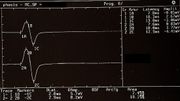

| 17:31, 26 February 2023 | Recovery cycle.jpeg (file) |  |

54 KB | 1 | |